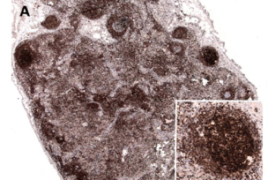

Das ALK-positive großzellig anaplastische T-Zell-Lymphom (ALK+-ALCL) ist durch die Translokation t(2;5)(p23;q35) charakterisiert, die zur Entstehung des Fusions-Proteins NPM-ALK führt. Die anaplastische Lymphom-Kinase (ALK) ist ein Mitglied der Insulinrezeptor-Familie mit Tyrosinkinase-Aktivität, deren konstitutive Aktivierung für die Initiierung der Lymphomgenese verantwortlich gemacht wird. NPM-ALK interagiert mit vielen Adaptor-Proteinen und aktiviert mehrere Signaltransduktions-Wege, die wichtig für das Zellwachstum, die Zelltransformation und das Überleben der Zelle sind. Wir untersuchen verschiedene ALK-abhängige Signalwege, um entscheidende Mechanismen der Tumorgenese zu identifizieren (regulierte Gene und miRNAs) und charakterisieren deren biologische Effekte durch funktionelle Analysen. In unseren Studien der letzten Jahre haben wir zum einen den Transkriptionsfaktor C/EBPβ (CCAAT/enhancer binding protein β) mittels funktionellen Gensilencing-Analysen als zentralen Faktor der ALK-vermittelten Onkogenese charakterisiert und verschiedene nachgeschaltete Proteine identifiziert, die unter anderem an Überleben, Proliferation und ribosomaler Biogenese der Tumorzellen beteiligt sind.

Ein anderer Aspekt ist die biologische Charakterisierung der an der ALCL-Pathogenese beteiligten microRNAs (miRNA). Wir untersuchen die ALK- oder C/EBPβ-abhängige miRNA-Expression in Zelllinien mittels Next Generation Sequencing, und verifizieren die Expression der Kandidaten-miRs an primären ALCL-Patientenfällen mit RT-qPCR. Interessante miRNAs können mit Hilfe von miRNA-Mimics in ALCL-Zelllinien überexprimiert werden, um deren Zielgene durch Transkriptom-Analysen mittels Next Generation Sequencing zu ermitteln. Unsere Studien zielen darauf ab, wichtige miRNAs oder deren Zielgene zu identifizieren, die letztendlich als Angriffspunkt für eine gezielte Therapie und/oder für die Optimierung bestehender Therapie-Strategien genutzt werden können.

Das Follikuläre Lymphom gehört zu den B-Zell Non-Hodgkin-Lymphomen und ist durch die Translokation t(14;18)(q32;q21) charakterisiert, die zu einer konstitutiven Expression des anti-apoptotischen Proteins BCL2 führt. Des Weiteren ist das FL durch eine Vielzahl an sekundären genetischen Veränderungen gekennzeichnet, die in 70-90% der FL-Fälle gefunden werden.

Das Follikuläre Lymphom in situ (FLIS), das durch Studien der letzten Jahre als frühe Vorläuferform des FL gilt, aber nicht konsekutiv zum FL transformiert, zeigt die selbe Translokation wie das manifeste FL, doch fehlen diesem sekundäre genetische Veränderungen. Wir gehen davon aus, dass der Erwerb weiterer molekularer Alterationen für die maligne Transformation des FLIS in das manifeste FL notwendig ist. Ziel unserer Arbeit ist daher die Identifikation genetischer Veränderungen, die im FL und auch im FLIS bzw. nicht im FLIS vorliegen.